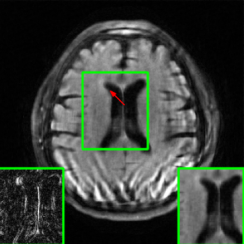

Figure 10 presents visual comparison of image reconstructions and their associated reconstruction errors within a closely examined region. Each image in the figure includes two inset panels in the bottom-left and bottom-right corners. The bottom-left inset panel, enclosed within a green bounding box, serves as a reference for the region of interest in the image. In contrast, the bottom-right inset panel depicts an error map in relation to the ground truth. Notably, our method stands out in its ability to capture more features from the original image, surpassing the performance of alternative methods (as also evident from the reported PSNR values).

Here, we employ the fastMRI+ dataset to assess our approach’s image reconstruction capability. For the training phase, we employ the original fastMRI brain dataset, which excludes lesion cases, as the basis for training all methods. During the testing phase, however, we utilize the lesion dataset. Table II shows the results, where our method reports the highest PSNR and SSIM values compared to other baselines. It is important to highlight that, unlike the cases of additive k-space noise and training/testing sampling protocol and undersampling rate disparities, the improvements observed from utilizing our method with unseen lesions are somewhat marginal as seen from the average PSNR and SSIM results (at least 1.2 dB PSNR improvement when compared to the 2nd best results). Additionally, visualizations are provided Figure 13 where we highlight the nonspecific white matter lesion area. As observed, both visually and in terms of PSNR values, our approach reports improved results when compared to the other baselines.